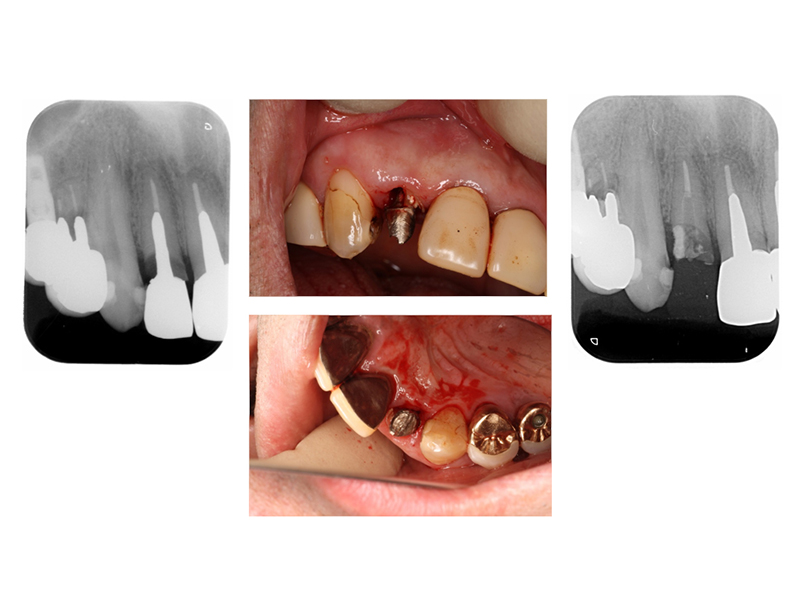

▼ ケース6.矯正的挺出

矯正開始前

矯正開始

矯正終了

補綴終了

矯正開始前、矯正終了時、補綴終了